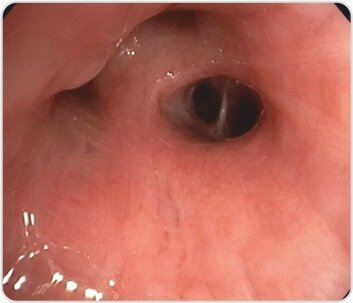

الشكل 3: الغشاء المخاطي الصحي